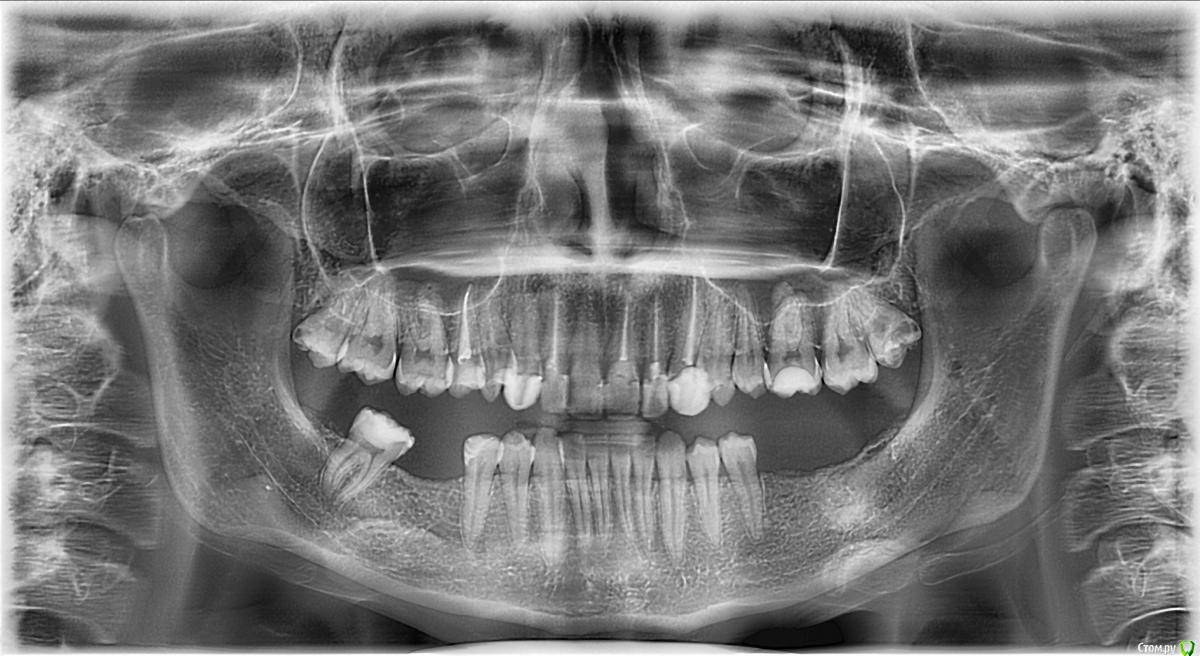

Beijaflor Опубликовано 18 июля, 2019 Поделиться Опубликовано 18 июля, 2019 (изменено) Доброго времени суток.Еще в феврале начало болеть лицо с левой стороны, жжение в щеке, слезился и болел глаз, иногда отдавало в ухо, было не ясно откуда идет, по ощущениям то ли от 8-ки,то ли между 3 и 4-кой. Я делала аппликации в рот ( димексид,дексометазон,вода для инъекций). На 2-3 день прошло. Было потом в марте, делала снова.Сейчас две недели болит лицо снова, боль локализуется преимущественно над тройкой и четверкой и под глазом, но при этом и над 8-кой болит тоже. Сначала больше похоже на дискомфорт было в щеке и над зубами, а сегодня уже прямо ноет. Найз не помогает совсем. Была у стоматолога вчера, залечили 6-ку с глубокой дыркой. Но нигде пульпита нет, десна в порядке. Что болит не ясно. 3-ка слева залечена в ноябре, была гранулема. Вылечили. В 4-ке со стороны 3-ки есть кариес, будем лечить. Но по снимку тоже с пульпой все хорошо. Сами зубы не болят. Боль выше, над зубами,у корней. Отдает в глаз порой или будто жжение внутри. Что это может быть? Снимок прилагаю. Буду благодарна за помощь. Изменено 18 июля, 2019 пользователем Beijaflor Ссылка на комментарий

Jurai Опубликовано 19 июля, 2019 Поделиться Опубликовано 19 июля, 2019 Так в восьмом слева цветет пульпит, судя по снимку. Удалить. 2 Ссылка на комментарий

Beijaflor Опубликовано 22 июля, 2019 Автор Поделиться Опубликовано 22 июля, 2019 Так в восьмом слева цветет пульпит, судя по снимку. Удалить. Пока что пульпита нет, дырку врач проверял инструментами, боли никакой не ощущается. Но ее все равно булем удалять, кариес возник недавно и очень быстро прогрессирует, так как растет в сторону щеки, качественная чистка затруднена. Ссылка на комментарий